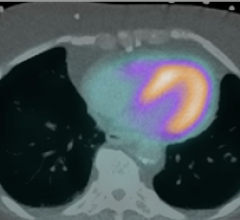

December 14, 2022 — CytoSite Bio, a company developing precision imaging products that determine patient response to ...